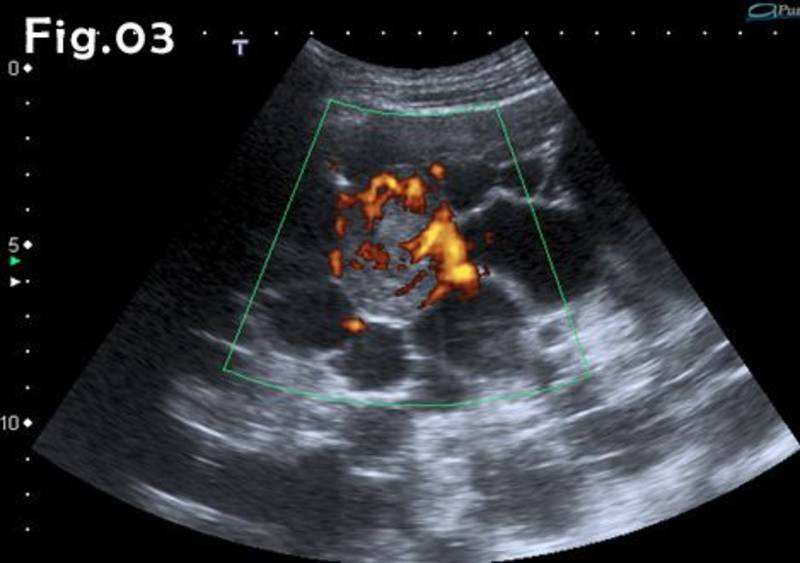

Kreisā nierē papildus tika atrasta arī kompleksa cistiska masa 114 mm diametrā un blīva masa, kuras izmēri bija 72x41x38 mm (2. attēls).

Krāsu Doplera izmeklējumā blīvā maisa bija bagātīgi vaskularizēta (3. attēls). Kompleksajā cistā vaskularizācija netika novērota.

Blīvā masa kreisajā nierē tika aprakstīta kā iespējama nieru šūnu karcinoma un pacientam veica kreisās puses nefrektomiju. Parenhīmas saglabājoša operācija netika veikta, jo pacientam pēdējos mēnešos jau bija uzsākta hemodialīze. Histoloģiskais slēdziens - nieru šūnu karcinoma, hromofobais tips.